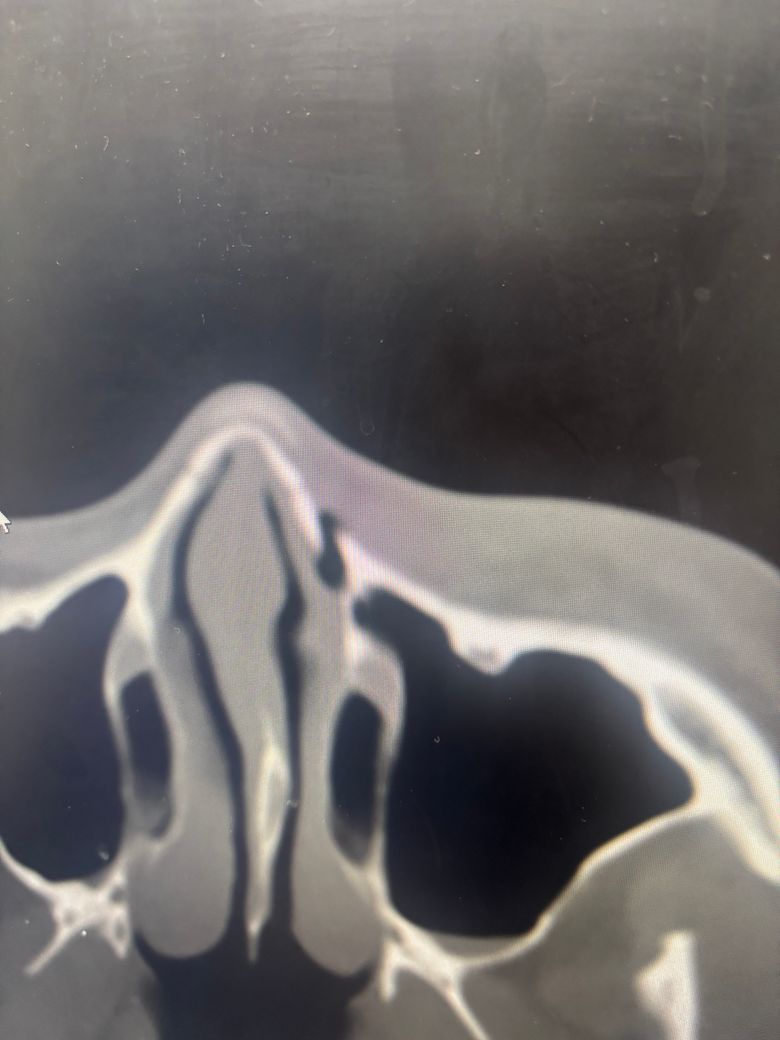

• 1번 째 사진

폭행으로 인해 코 골절 / 위턱 골절 판정을 받았는데

코는 골절이 좀 되서 수술을 해야하고

지금 코 뼈도 심하게 금이 간건지에대해사도 궁금함미다 진료를 받을때 진료해주신 교수님이